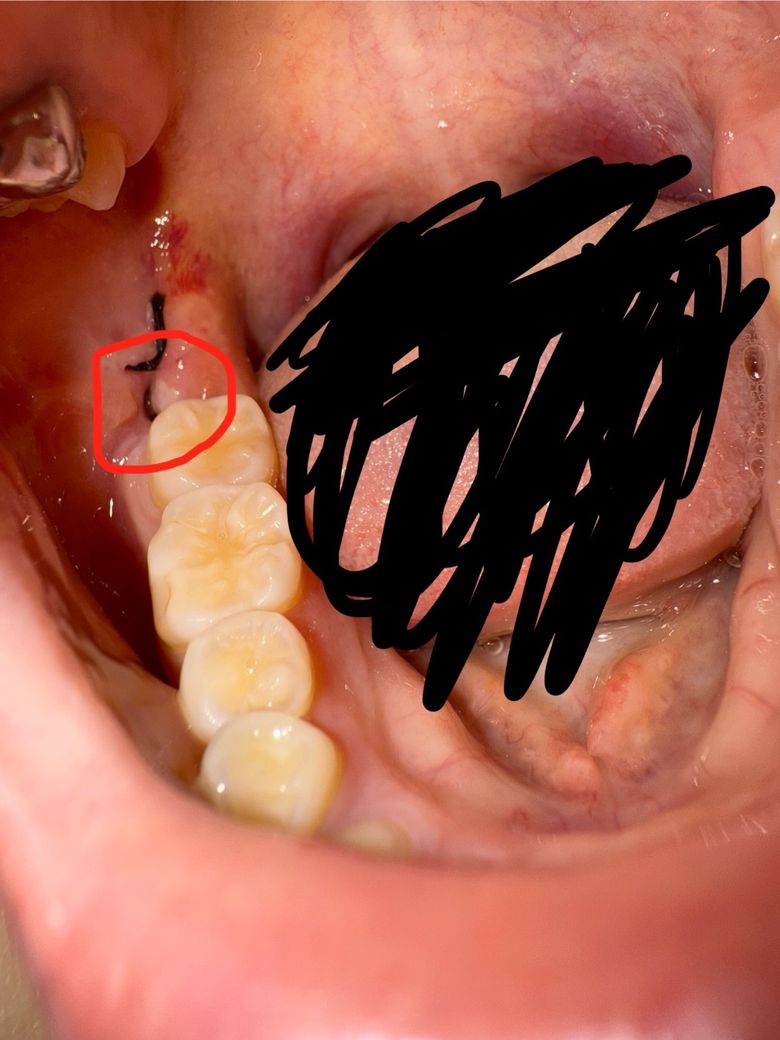

사랑니 발치 후 잇몸에 하얗게 올라온 것 정상인가요?

사랑니 발치 후 4일이 지났고, 병원에서 하지 말라는 거 다 안 했습니다. 근데 잇몸을 자세히 보니 안이 하얗게 되어있어서 걱정됩니다. 아프진 않은데 염증인가요?

잘 아물고 있는거 맞나요 ㅠㅠ

사랑니를 발치하게 되면 발치한 부위에 상처가 남아 있게 됩니다. 위로는 가피 등이 형성될 수 있습니다. 크게 문제가 되진 않을 것으로 생각되나 신경이 쓰이거나 해당 부위가 불편하다면 치과에서 진료를 받아보는 것을 권유 드립니다.

사진상으로 보면 상처가 잘 아물고 잇는거 같습니다. 자극만 가지 않도록 해주시면될것같습니다.

사진상 봤을때 약간의 염증양상은 있습니다만 발치 부위 자체는 치유가 더디거나 그렇지는 않습니다.